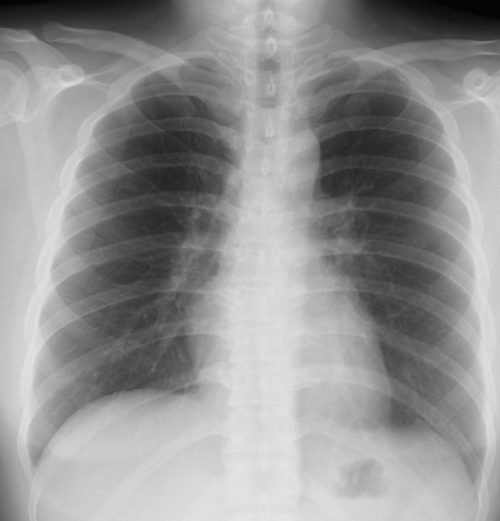

外来でよくみられる肺炎、マイコ・クラミジア・肺炎球菌・ウイルス(RSウイルス・hMPV・インフルエンザウイルスA・B)について実際に経験、外来で治癒した症例を提示します。軽症な変化のものが大多数ですが中には重症なものも紛れていて、注意が必要になります。

【マイコプラズマ肺炎】